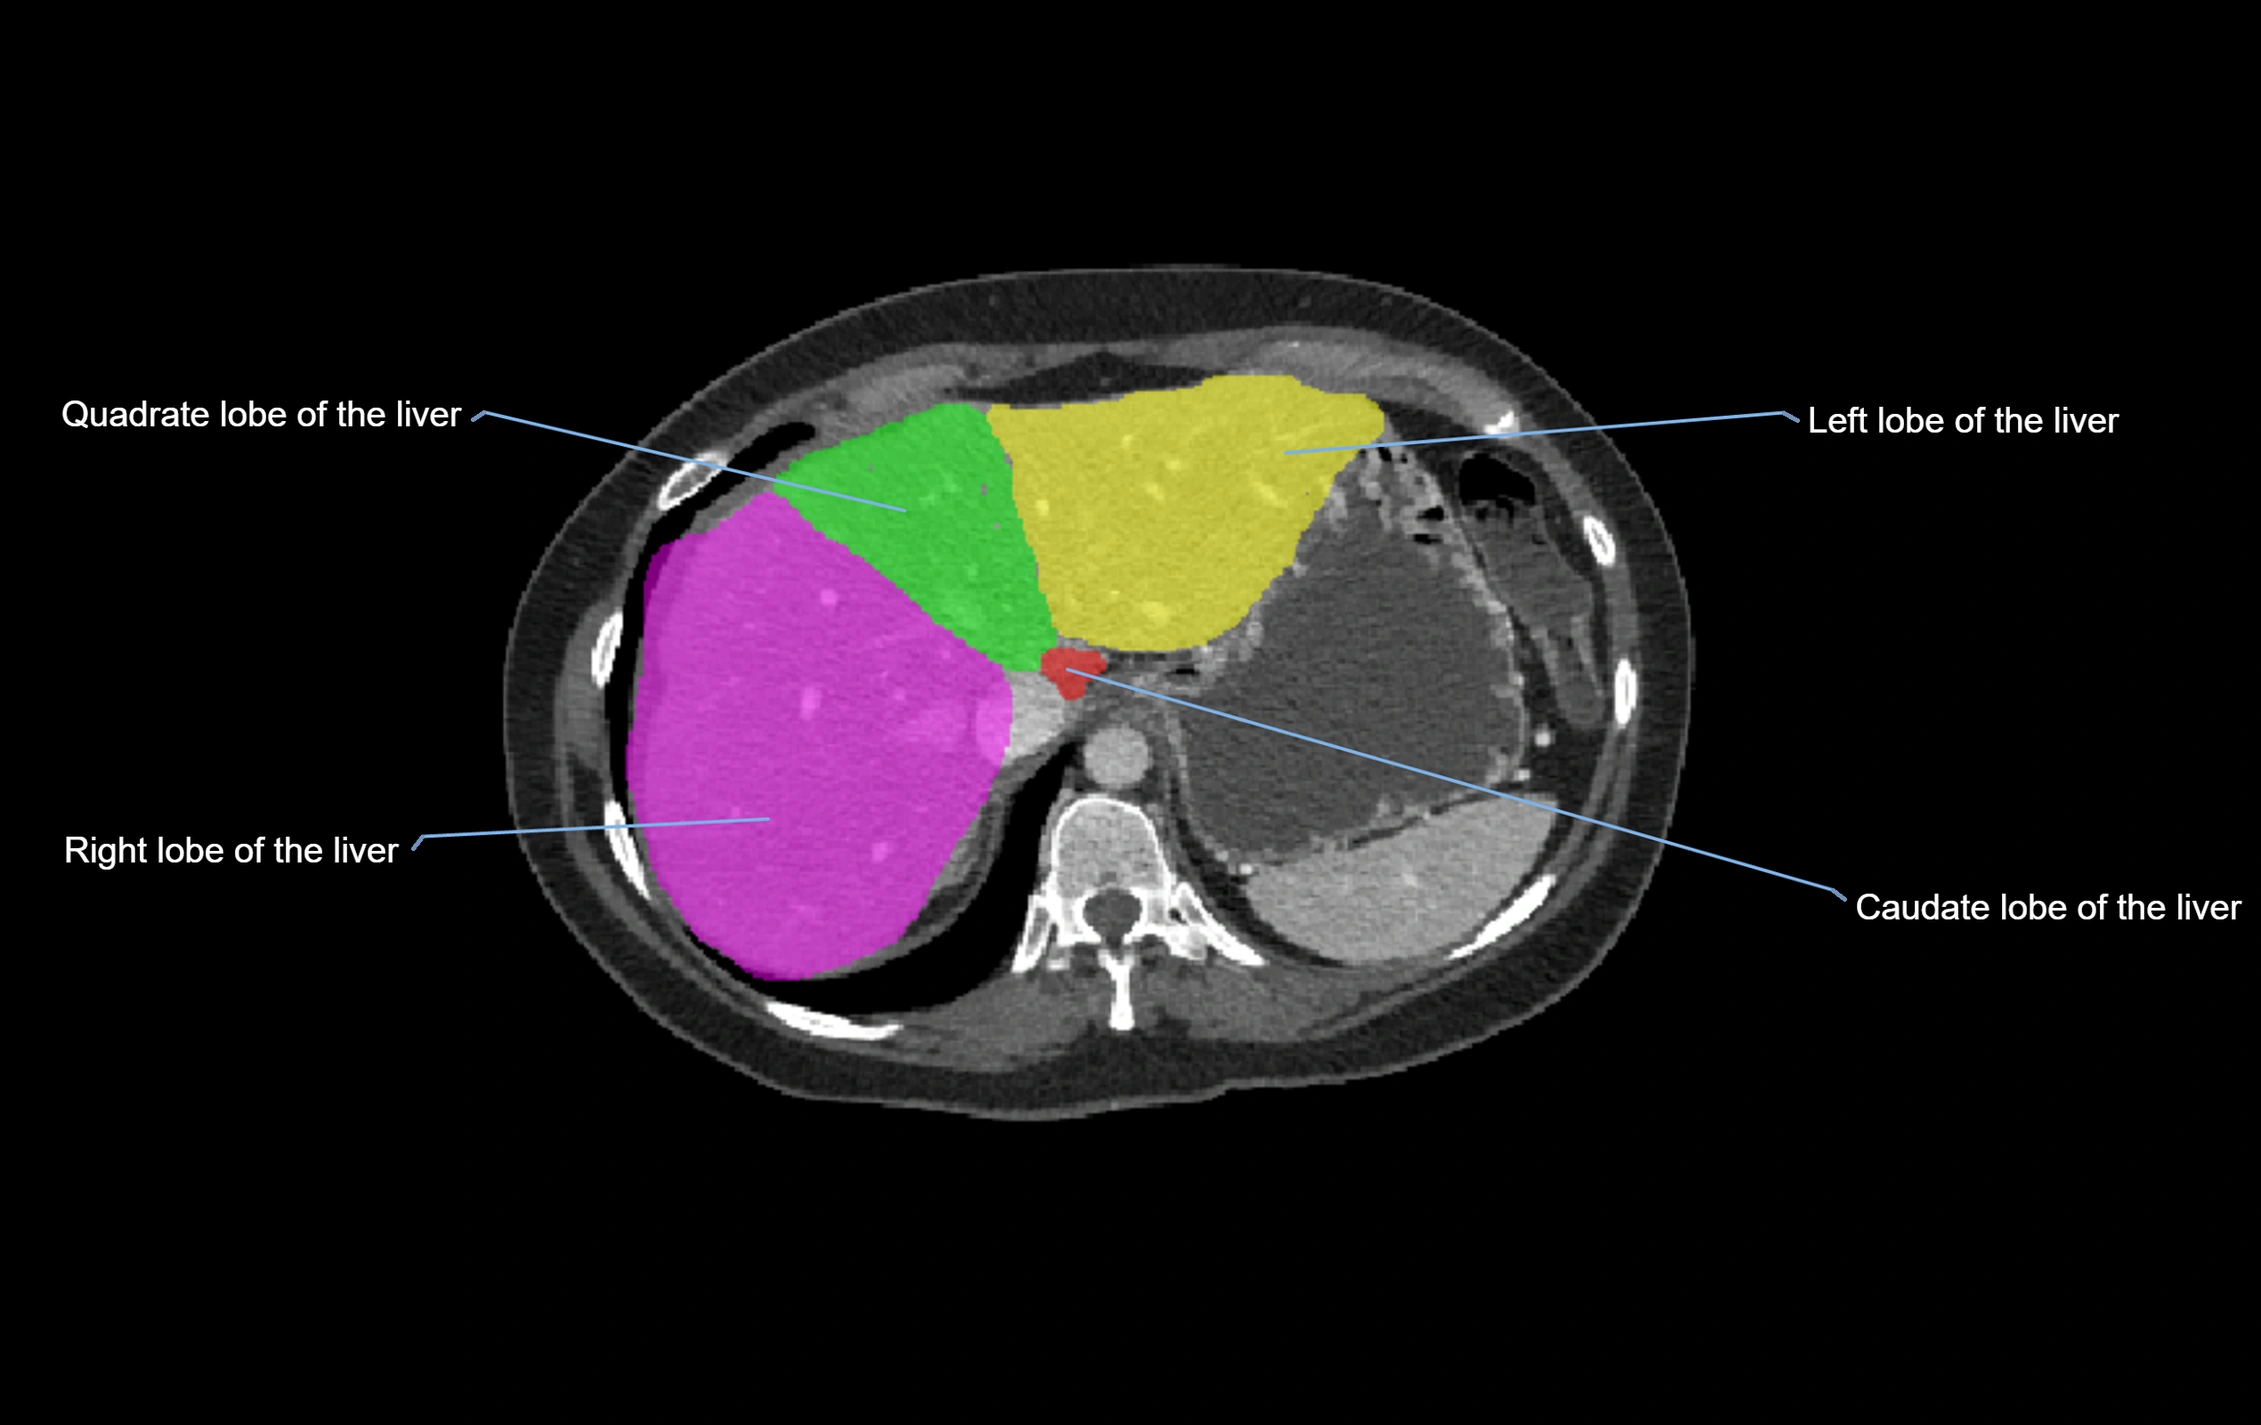

The caudate lobe of the liver is a distinct anatomical subdivision of the liver, designated as segment I in Couinaud’s classification. It lies on the posterior surface of the liver, between the fissure for the ligamentum venosum (left boundary) and the groove for the inferior vena cava (IVC) (right boundary). Superiorly, it is related to the posterior liver surface, and inferiorly it is separated from the left lobe by the porta hepatis.

CT Appearance

CT Pre-Contrast:

• Caudate lobe appears as a soft-tissue density, isodense to the rest of the liver

• Enlargement may be appreciated in cirrhosis or Budd–Chiari syndrome

CT Post-Contrast:

• Homogeneous enhancement in the portal venous phase, similar to rest of liver

• Independent venous drainage into the IVC may be visualized

• Lesions follow characteristic CT enhancement patterns (HCC: arterial hyperenhancement with washout; hemangiomas: peripheral nodular enhancement with centripetal fill-in)

CT Venous Phase (functional significance):

• Caudate lobe often enhances relatively more than other lobes in Budd–Chiari syndrome, due to preserved venous outflow

CT Image